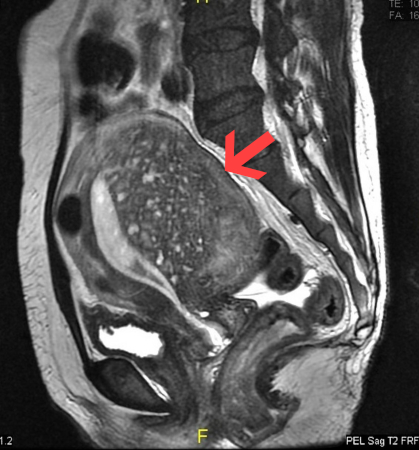

Adenomyosis

Sagittal MRI of a woman's pelvis showing a uterus with adenomyosis in the posterior wall. Gross enlargement of the posterior wall is noted, with many foci of hyperintensity

Case courtesy of Dr Varun Babu, Radiopaedia.org. From the case rID: 43504; reproduced under the Creative Commons CC BY-SA 4.0 license (https://creativecommons.org/licenses/by-sa/4.0/ )